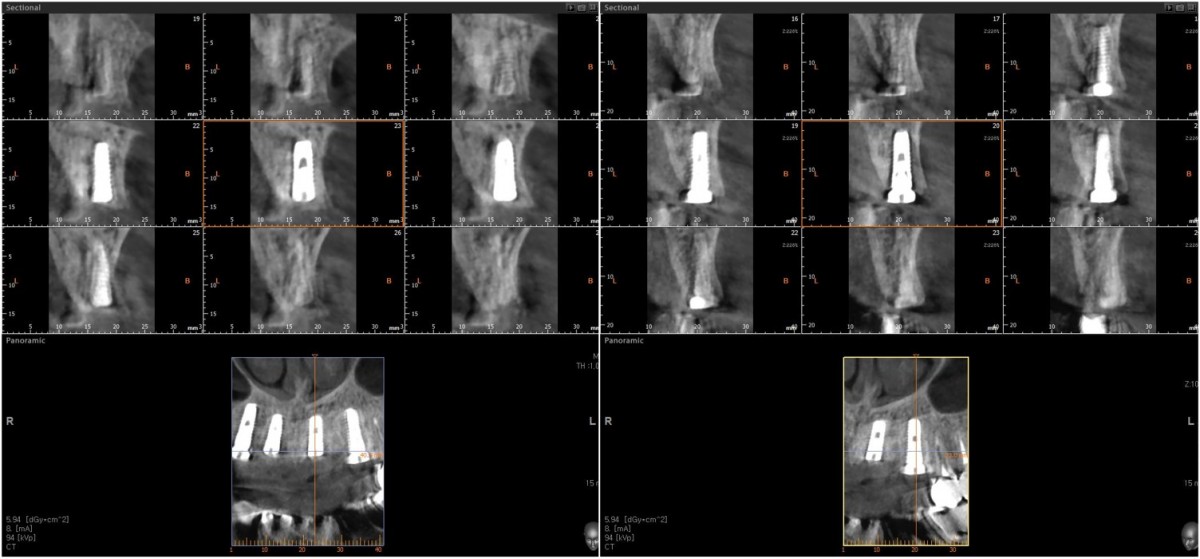

Anterior implant placement with Arum implant system in the maxilla.

▲Fixture to be placed. Arum® implant NB1

▲Implant placement GBR

▲GBR(Xenograft).